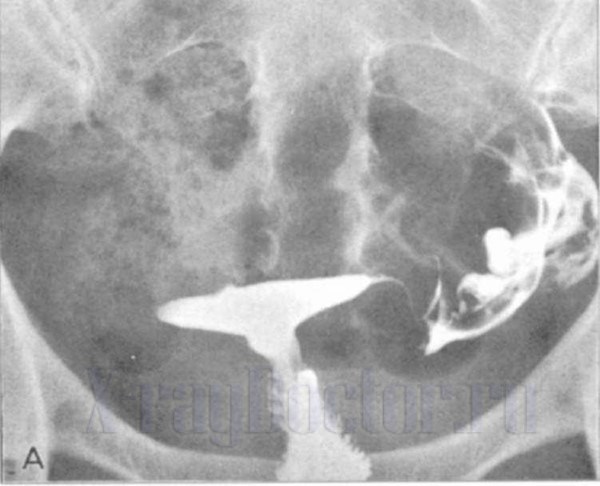

Чтобы исключить наличие других сопутствующих заболеваний, проводятся анализы крови и бактериологические исследования. Также информативным является рентгенологическое исследование с контрастом, которое выполняется с использованием специальных веществ, вводимых в мочевой пузырь через уретру. Этот метод позволяет получить уникальные изображения, способствующие определению локализации. В некоторых случаях может потребоваться эндоскопическое исследование влагалища, а также компьютерная томография.